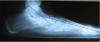

Numerous gait studies have been conducted on patients with adult-acquired flatfoot, particularly those with stage II deformity.

27-29 These studies have shown postural changes that one would not see in asymptomatic feet that are flat and pronated. Instead, stage II adult-acquired flatfoot deformity consistently shows a combination of excessive hindfoot eversion, lowering of the medial longitudinal arch and significant abduction of the forefoot.